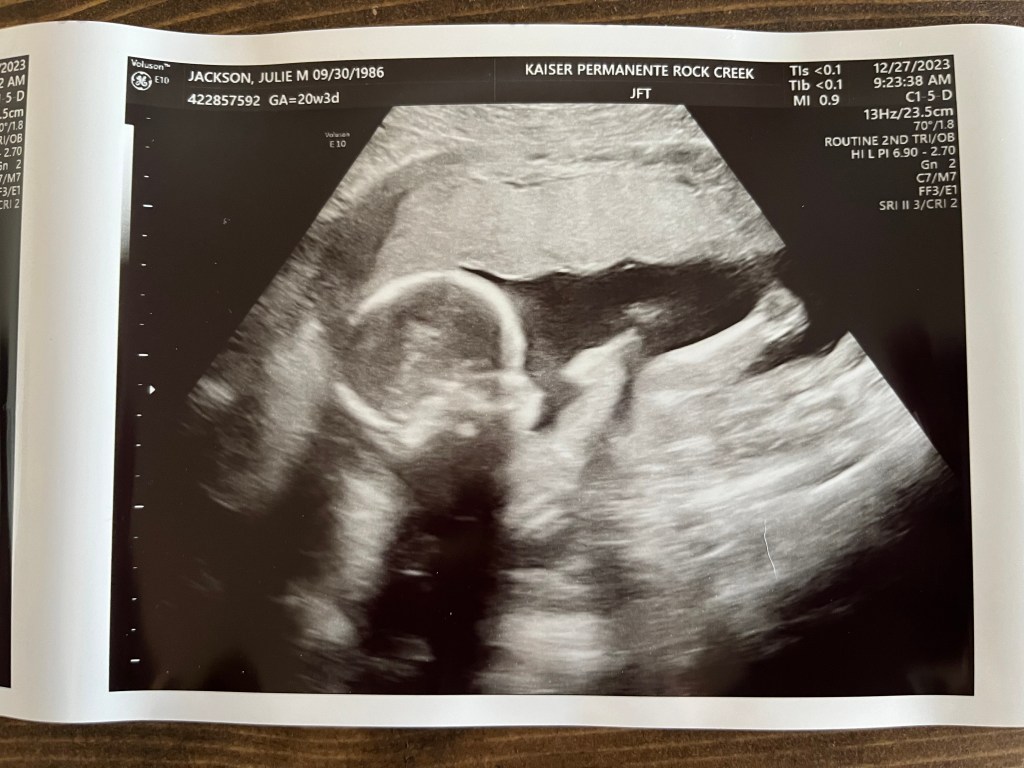

On Wednesday, Dec. 27, we had our anatomy/3D ultrasound, and everything is looking good with Baby Boy Jackson. I’ll share more details about the appointment after next week’s special post.

And just to keep you tied over until then, here’s one of the images from that scan!

We did learn why I hadn’t been feeling as much movement as I thought I should.

I have an anterior placenta, so it’s on the front of my uterus (rather than back toward my spine). This dampens what you can feel until a little later on. But again, more details (and pics) to come from this appointment in an upcoming blog.